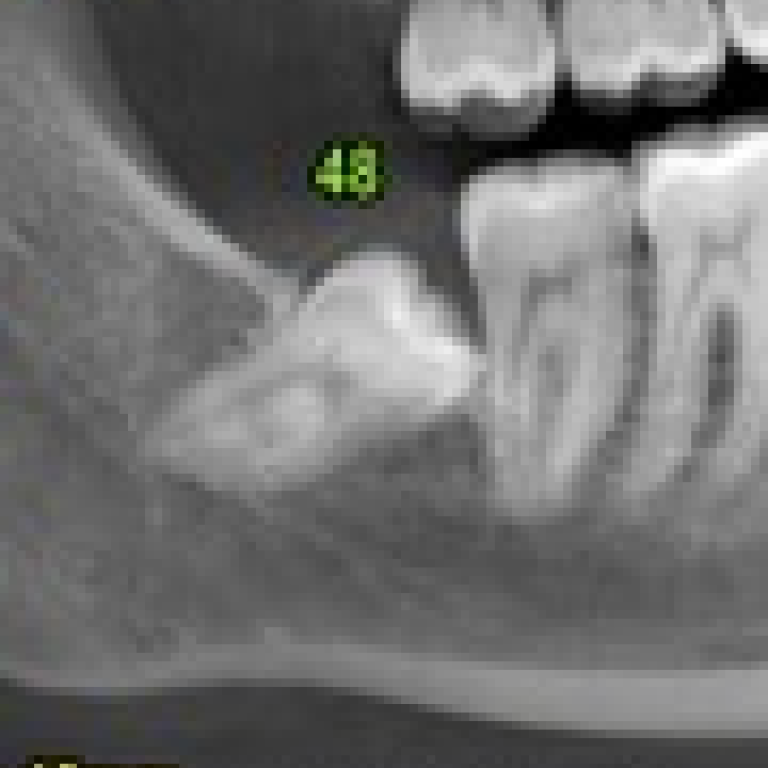

[Immagine di un dente del giudizio in contiguità con il canale mandibolare] La lesione del nervo alveolare inferiore …

La disodontiasi è un fenomeno doloroso associato ad un'alterazione del normale processo eruttivo dei denti. Gli elementi dentari …